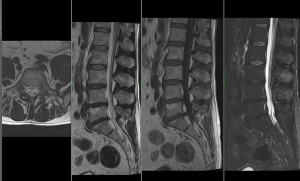

MR páteře

Degenerativní onemocnění (ploténky, vazy, mícha, míšní nervy), metoda volby u nádorových a zánětlivých onemocnění míchy, spinální traumata – akutní vyšetření.